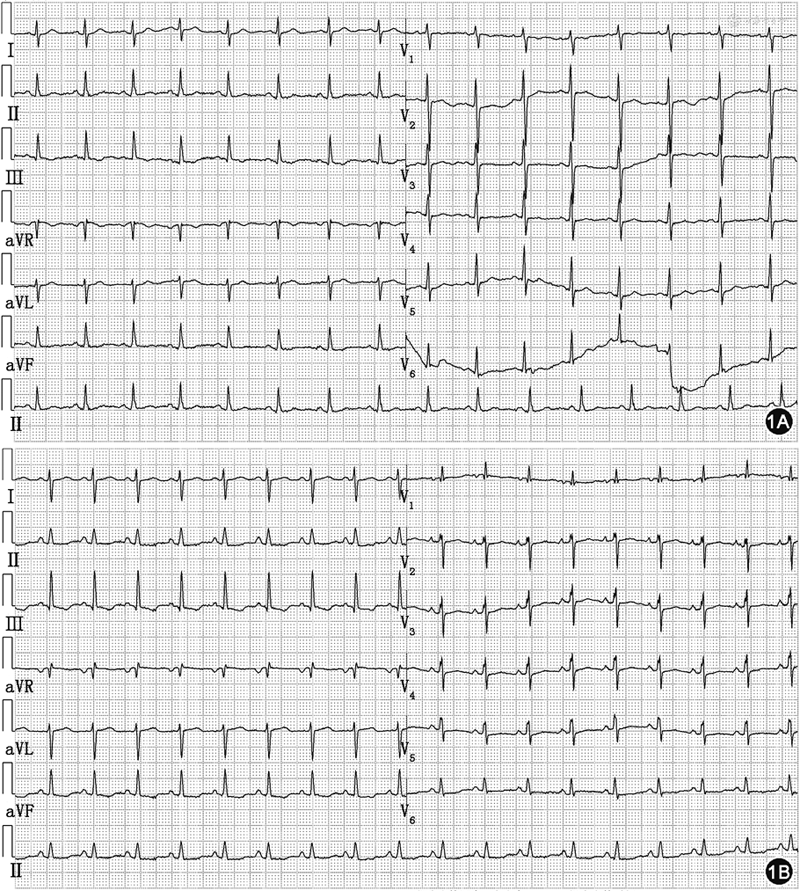

患者,女,28岁。因“妊娠30周零6日,活动时气短伴夜间平卧困难5日”于2023年3月18日来我院就诊。2022年11月30日患者因妊娠15周合并系统性红斑狼疮曾来我院产科就诊,产科超声提示胎儿无明显异常,由于系统性红斑狼疮未得到规范治疗建议终止妊娠,患者及家属拒绝,后未规律产检。2023年3月13日(妊娠30周零1日)时出现活动时气短,休息后可减轻,但不能完全缓解,气短进行性加重,3月17日时出现夜间平卧困难,伴心悸、背痛,遂于2023年3月18日就诊于我院急诊。既往确诊系统性红斑狼疮14年,累及皮肤和肾脏;2021年首次妊娠16周时发现高血压,产后血压恢复正常;否认糖尿病、冠心病等慢性病病史。入院体格检查:一般情况尚可,体温36.8 ℃,脉搏102次/min,呼吸20次/min,血压110/92 mmHg(1 mmHg=0.133 kPa),脉搏氧饱和度98%,颈静脉无怒张,四肢无水肿,双肺呼吸音清,未闻及干湿啰音,心率102次/min,律齐,P2>A2,未闻及明显杂音,腹部膨隆,可触及胎体,可闻及胎心。急诊入室立即行实验室检验:D-二聚体 1.16 g/L(0~0.55 g/L),高敏肌钙蛋白I 33 ng/L(≤34 ng/L),N末端B型利钠肽原(N-terminal pro-B-type natriuretic peptide,NT-proBNP)9 630 ng/L(0~125 ng/L);血气分析:pH 7.43(7.35~7.45),二氧化碳分压11 mmHg(35~45 mmHg),氧分压113 mmHg(83~108 mmHg),血氧饱和度98%(95%~99%),碳酸氢根浓度8.8 mmol/L(22.0~27.0 mmol/L),乳酸8.3 mmol/L(0.5~1.6 mmol/L);电解质正常;补体C3 0.474 g/L(0.730~1.460 g/L),补体C4 0.105 g/L(0.100~0.400 g/L),抗双链DNA抗体5.60 U/ml(阴性:<24.00 U/ml)。心电图提示:窦性心动过速,电轴右偏,V1导联R/s>1(图1)。床旁超声心动图提示:右心室前后径35 mm,左心室舒张末期内径32 mm,左心室射血分数66%,右心增大,右心室室壁活动降低,估测肺动脉收缩压76 mmHg,重度肺动脉高压。CT肺动脉造影提示:未见明显肺动脉栓塞征象,右心明显增大,左心受压,肺动脉高压、右心压力增高可能大(图2)。产科超声提示:单胎,胎头位于脐上,可见胎心搏动。

经上述积极治疗后患者病情逐渐好转,神志清晰,生命体征稳定,高敏肌钙蛋白I及NT-proBNP逐渐回落至正常(图4),床旁胸片提示心脏逐渐缩小(图5),超声心动图提示右心室逐渐缩小,左心室舒张末期内径逐渐增大,估测肺动脉收缩压明显下降(表1),补体C3恢复正常(表2),脑脊液蛋白降至0.77 g/L,于4月7日拔除气管插管,于4月19日撤离ECMO,4月22日停用所有血管活性药物,患者循环稳定,系统性红斑狼疮病情缓解,一般情况可,5月16日带药出院。病例报告内容已获患者知情同意。